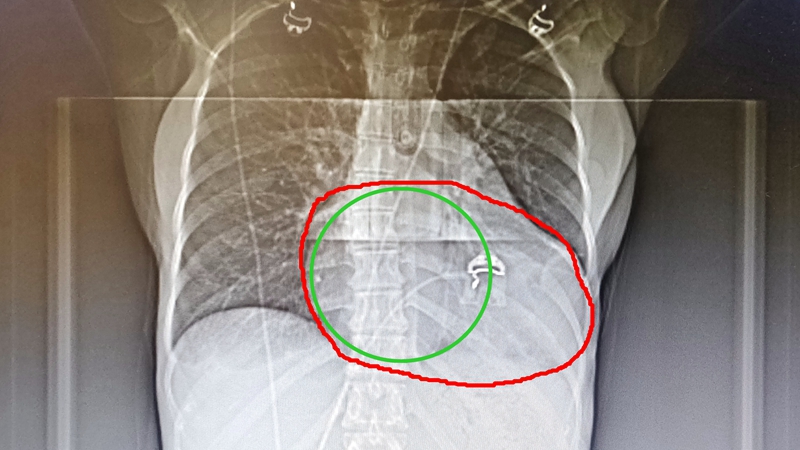

心电图检查显示III度房室传导阻滞,QRS波间期达166ms,远超120ms的正常值,这说明其心脏左右心室收缩不同步,心脏彩超检查报告显示,她的心脏是正常人的2倍大,收缩功能不足,不及正常人的一半,且左右心室收缩不同步,随时有猝死的风险。

【红圈部分为患者心脏,是绿圈(正常人)的2倍】